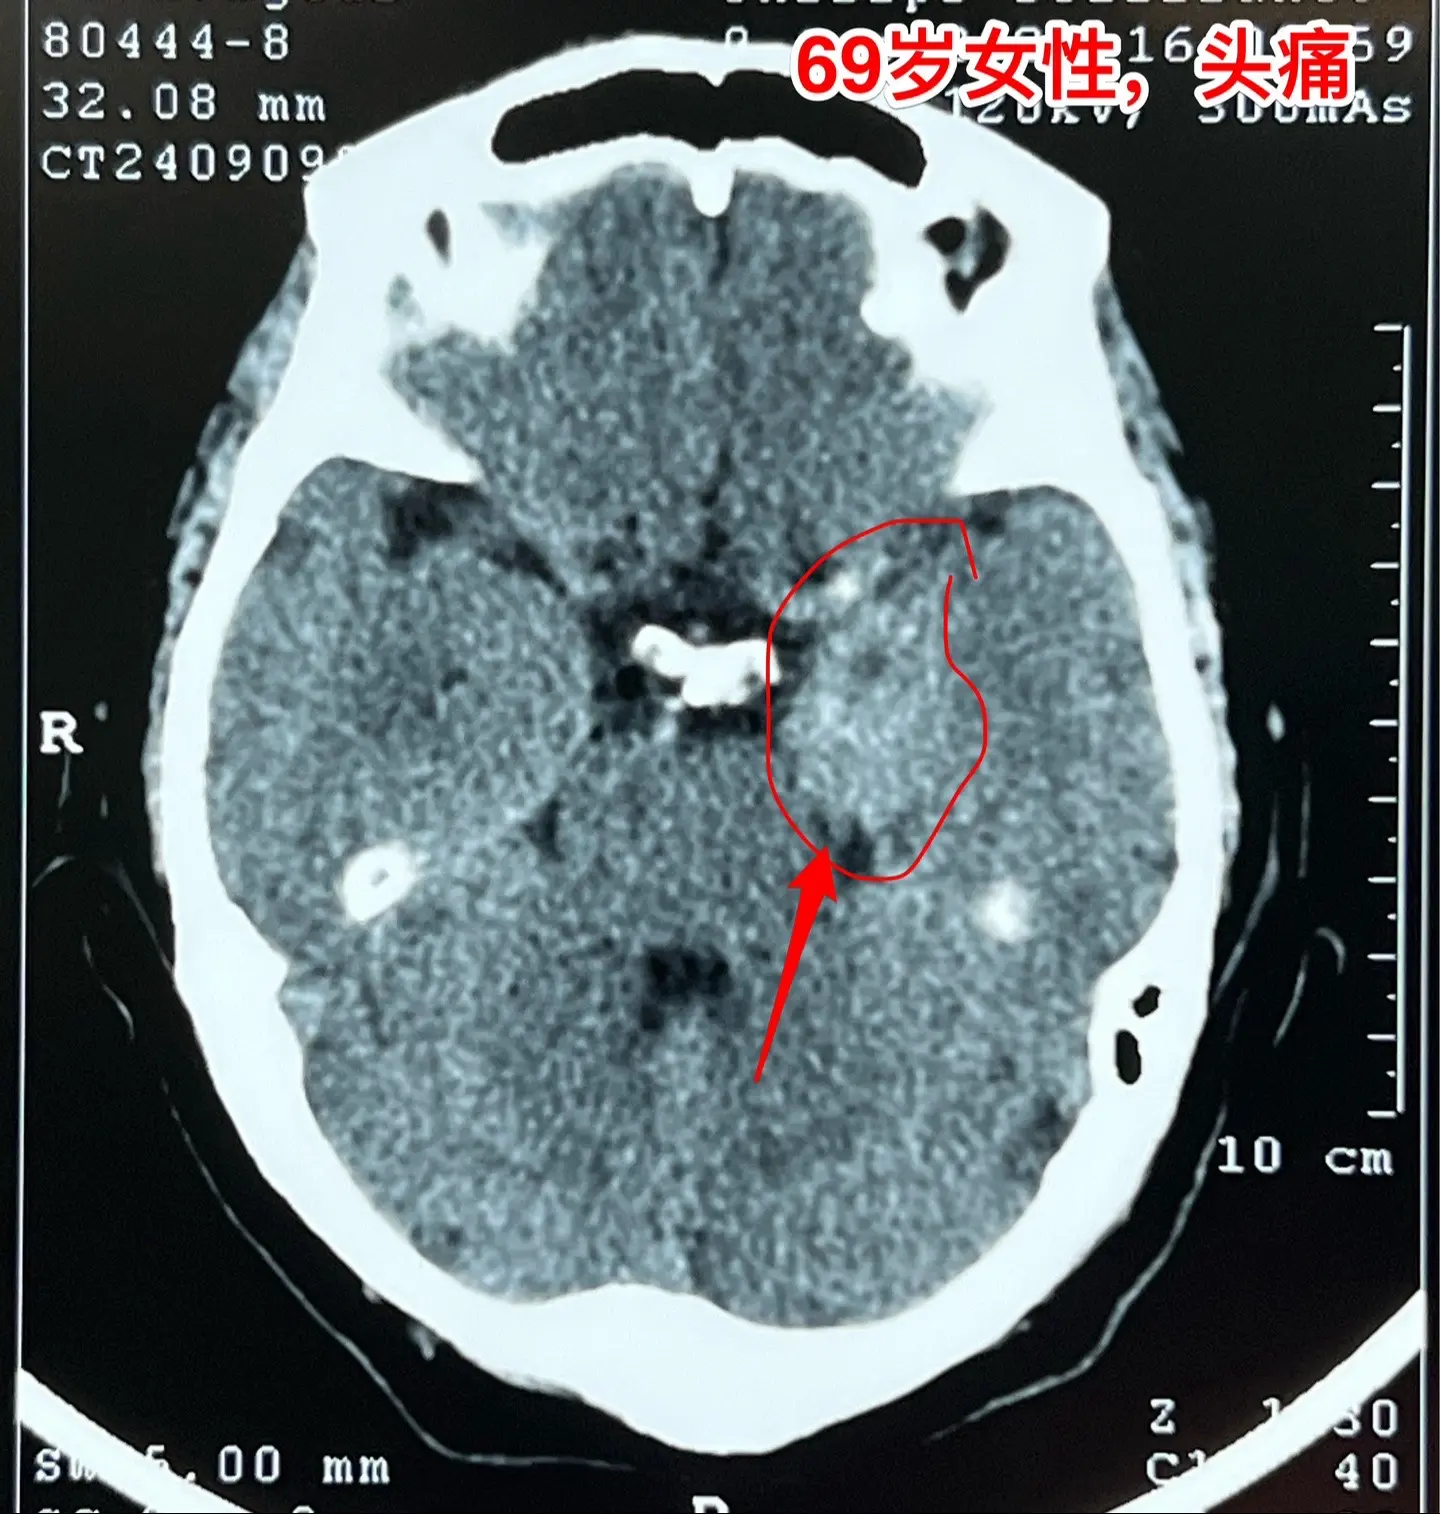

海绵窦区神经鞘瘤,是良性肿瘤。69岁青岛市老太太经常感到头痛,不太剧烈,没有专门去检查。九月份检查脑部磁共振发现左侧海绵窦长了肿瘤。在我院住院后作了强化磁共振,看见左侧海绵窦内有个大肿瘤,见图,考虑是神经鞘瘤,神经鞘瘤是良性肿瘤,如果完全切除了就可以治愈。 老太太有两个女儿,积极要求给她作手术。69岁年龄还是有点大,手术是有风险的! 9月12日下午四点开始进入手术室,手术持续到13日凌晨才结束。手术过程很顺利,肿瘤得到完全切除。今天看见老太太精神比较好,准备下地行走。神经鞘瘤海绵窦